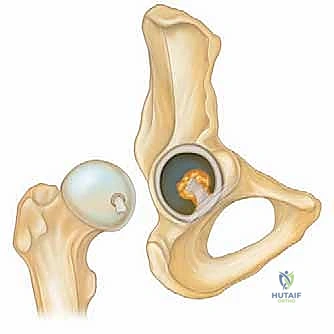

لفهم أهمية جراحة منظار الورك، يجب أولاً أن نفهم التكوين التشريحي المعقد لهذا المفصل الحيوي. مفصل الورك هو مفصل من نوع "الكرة والتجويف" (Ball and Socket Joint).

* الكرة: هي رأس عظمة الفخذ (Femoral Head).

* التجويف: هو جزء من عظمة الحوض يُعرف باسم الحُق (Acetabulum).

يُغطى كل من الكرة والتجويف بطبقة ناعمة من الغضروف المفصلي الذي يسمح للعظام بالانزلاق بسلاسة فوق بعضها البعض. كما يحيط بحافة التجويف حلقة من الغضروف الليفي القوي تُسمى الشفا الغضروفي (Labrum). يعمل الشفا كختم مطاطي يحافظ على السائل الزلالي داخل المفصل ويزيد من استقراره.

منظار الورك هو إجراء جراحي طفيف التوغل (Minimally Invasive) يتيح للجراح رؤية داخل مفصل الورك دون الحاجة إلى عمل شق جراحي كبير. يتم ذلك من خلال إدخال كاميرا دقيقة جداً (Arthroscope) متصلة بشاشة عرض عالية الدقة (4K) عبر شقوق صغيرة لا تتجاوز نصف سنتيمتر في الجلد.